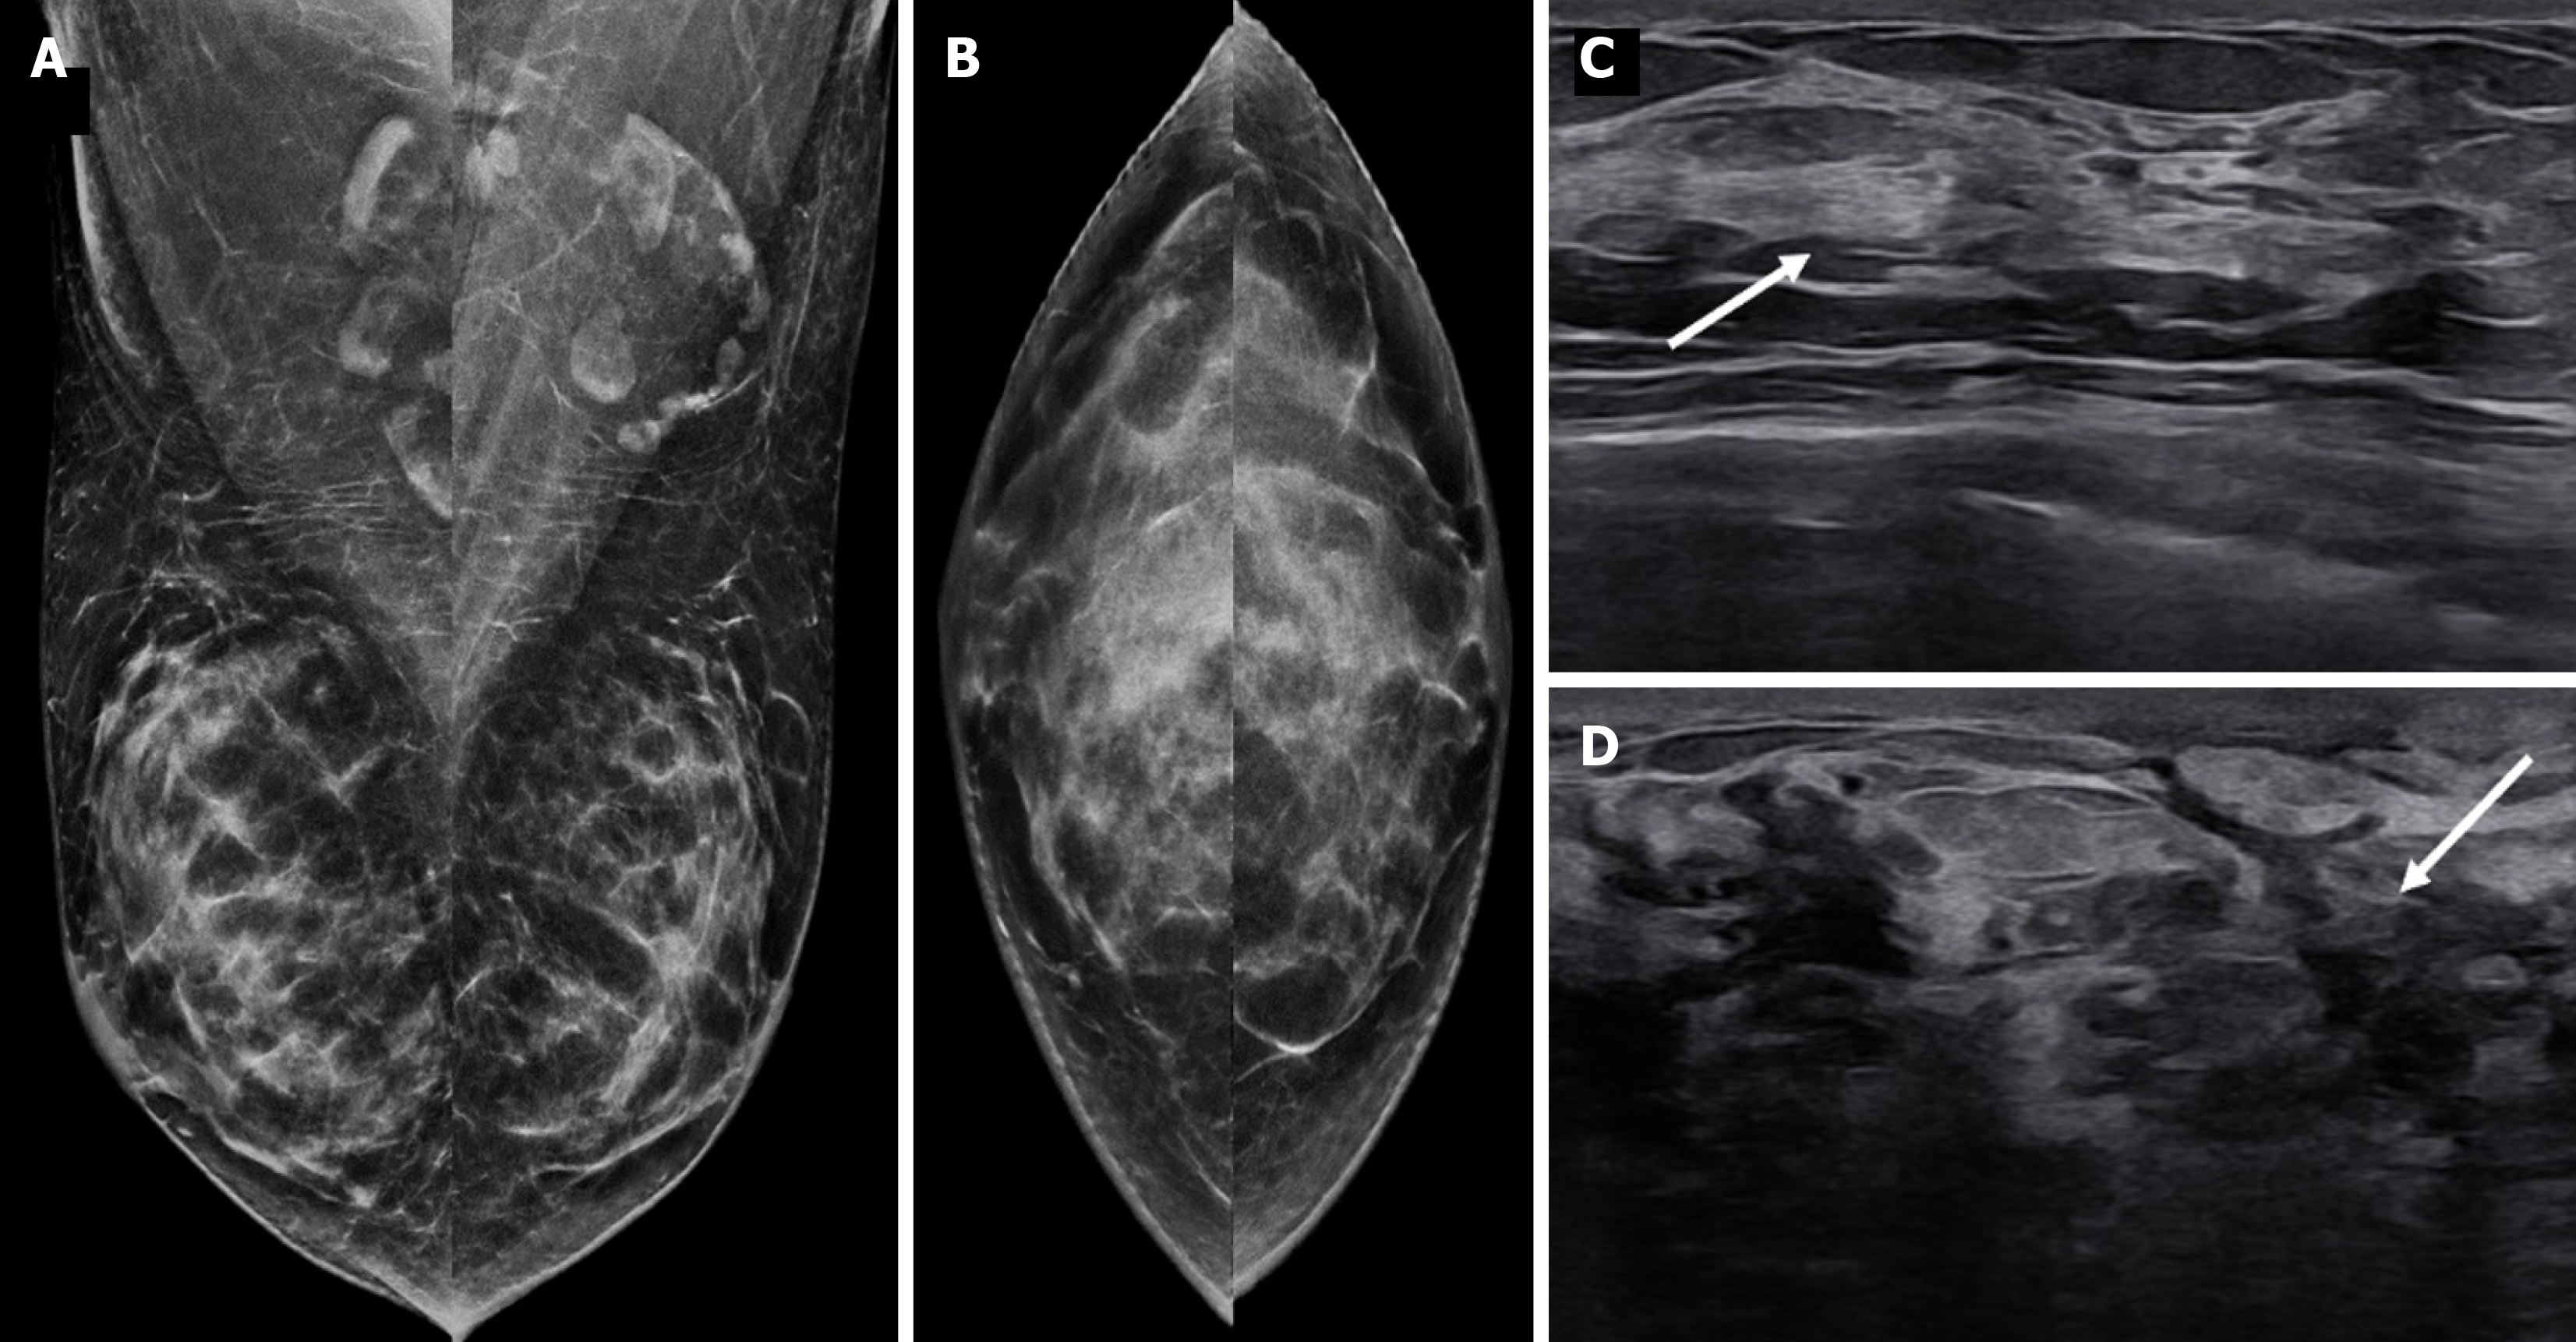

Figure 6 Diffuse gynecomastia in a 42-year-old male on estrogen therapy.

A: Mediolateral oblique; B: Craniocaudal mammography images showing a diffuse increase in breast density, with the male breast resembling the female breast; C and D: Ultrasound images showing diffuse deposition of glandular tissue (white arrows).